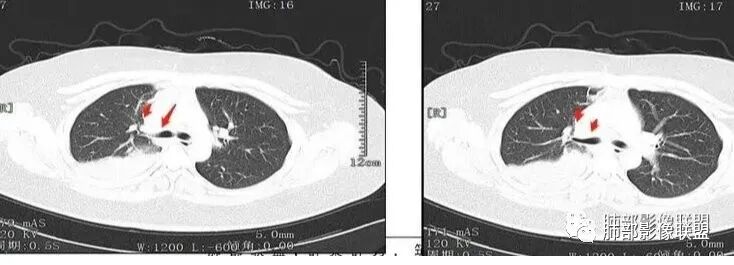

本病例特点是中叶病灶和下叶病灶不一样,支气管腔内的病灶又是怎么样的呢?我们要是有沿支气管重建的冠状位、矢状位会更有利于分析。第一,中叶病灶明显粘液样改变、低密度,且低密度区有占位效应、膨隆,确实要考虑粘液表皮样癌。第二,中叶和下叶支气管显示不出来,但血管显示出来了。中叶病灶血管稀疏、细小,下叶病灶血管粗大、走形正常。朝外肺不张实变,不是单纯的肺不张,肺不张一般体积明显缩小、血管聚拢,该病例肿瘤于其中成分不一样,所以上叶部分病灶考虑为下叶病灶占位效应及膈面向上推压引起,中叶萎缩。综合腔内堵塞、纵隔淋巴结肿大要考虑恶性。

支气管层面位置朝下强化明显,支气管腔内、远端是有差异的,腔内哪些是粘液?哪些是肺组织?是单纯实变?还是合并感染?还是外围都是病变?支气管腔内病变?

该病灶明显实变,需鉴别是内朝外,还是外朝内病变。该病灶内血管走形自然,肺门区血管无明显受压移位,且非起源于胸膜,不张肺组织或者不张肺组织夹杂炎性病变。而非典型肺炎型肺癌及外朝内的其他恶性病变。

内朝外病变是支气管腔内病变?还是支气管周围病变呢?如果支气管周围大恶性肿块灶,那其内血管也不应走形自然,应杂乱无章,所以只能是腔内病变引发支气管周围病变。

中央型类癌的影像学表现:

1.支气管腔内的圆形或卵圆形结节,边缘光整,也可浅分叶,完全位于支气管腔内。

2.病变管腔内的病变只占病变的一小部分,大部分位于管腔外,称为“冰山征”。

3.少数病例可沿支气管腔内长轴生长,呈指套样改变,可伴有小部分位于腔外,类似部分鳞癌的表现,但由于类癌供血丰富,较鳞癌血供丰富。

以上三种类型均可伴有阻塞性炎症或肺不张。